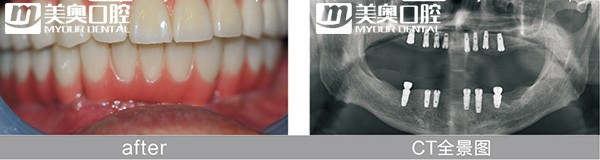

就在上个月,全口缺牙的63岁的徐先生在美奥口腔当天种牙,通过即拔即种即刻修复技术,拔除了2颗残根,同时种上种植体,安装牙冠,1天内就从缺牙到有牙;时隔一个星期,82岁的孟女士植人4颗植体,通过All-on-4即刻负重,当天戴上了整排牙,吃起了苹果;而上周末70岁的于先生因为需要种植6颗牙,计算了所有的费用,感觉有点负担,但因为购买了3个百元种牙福袋,获得了3颗免费的种植体,费用一下子减少了一半。

苏州美奥口腔院长王汉禹介绍,像徐先生这样的少量残冠无法保留的患者,他采用的是即拔即种,即刻负重的方式。在拔牙的同时植入植体,不必等待拔牙后3个月才种牙,植入种植体后也在当天就为他戴上了牙冠。

而像孟女士这样半口、全口的缺牙者,采取的是All-on-4即刻负重,半口缺牙只需在牙槽骨植入4颗植体,在当天戴上整排牙齿,恢复咀嚼力。将原本长达半年到1年的修复时期缩短到1天。不仅在戴牙当天可以吃饭,随着时间的推移,患者感到牙齿越来越有力。